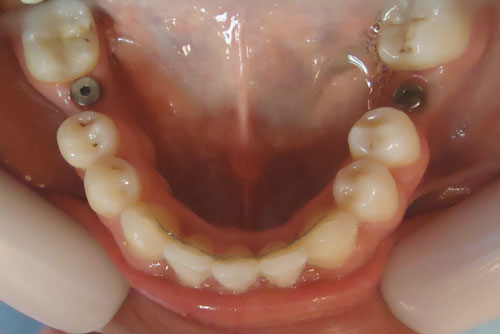

5-2-15implantes